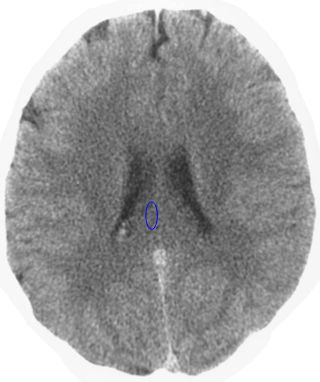

Which is the brain relais that is shown here? 25 Questions each cycle, try more!

Question 1 of 25